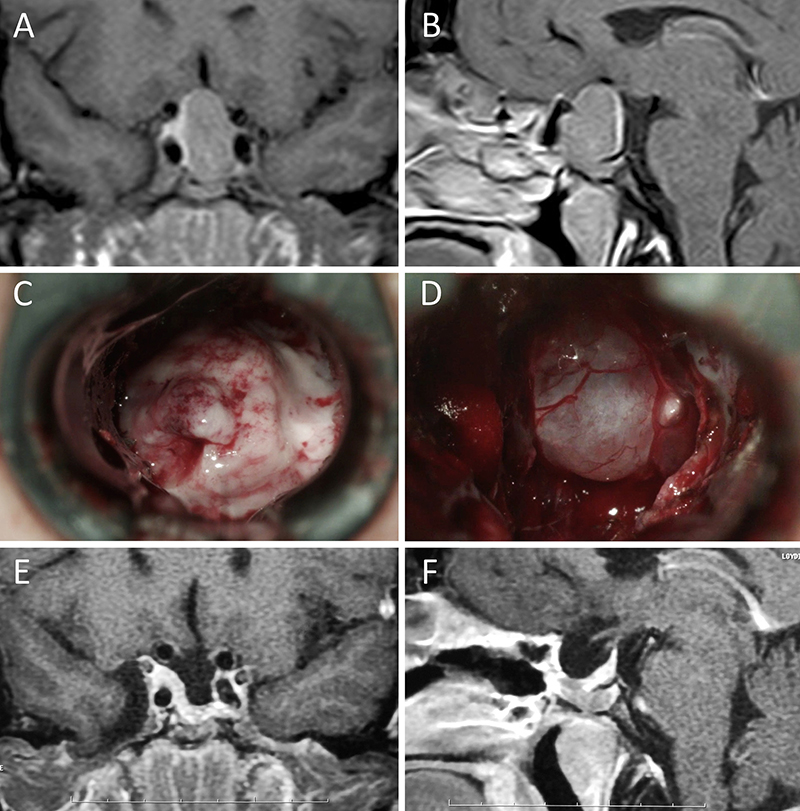

Figura 2: Macroadenoma no funcionante en mujer de 31 años. La paciente presentó en el preoperatorio déficit visual que mejoró tras la cirugía. A-B: RM preoperatoria; C-D: intraoperatorio; E-F: RM postoperatoria.

Figura 3: Macroadenoma no funcionante en un hombre de 64 años. El paciente presentó en el preoperatorio déficit visual que mejoró tras la cirugía. A-B: RM preoperatoria; C-D: intraoperatorio; E-F: RM postoperatoria.

Figura 4: Macroadenoma no funcionante en mujer de 32 años. La paciente presentó en el preoperatorio déficit visual que mejoró tras la cirugía. A-B: RM preoperatoria; C-D: intraoperatorio; E-F: RM postoperatoria.